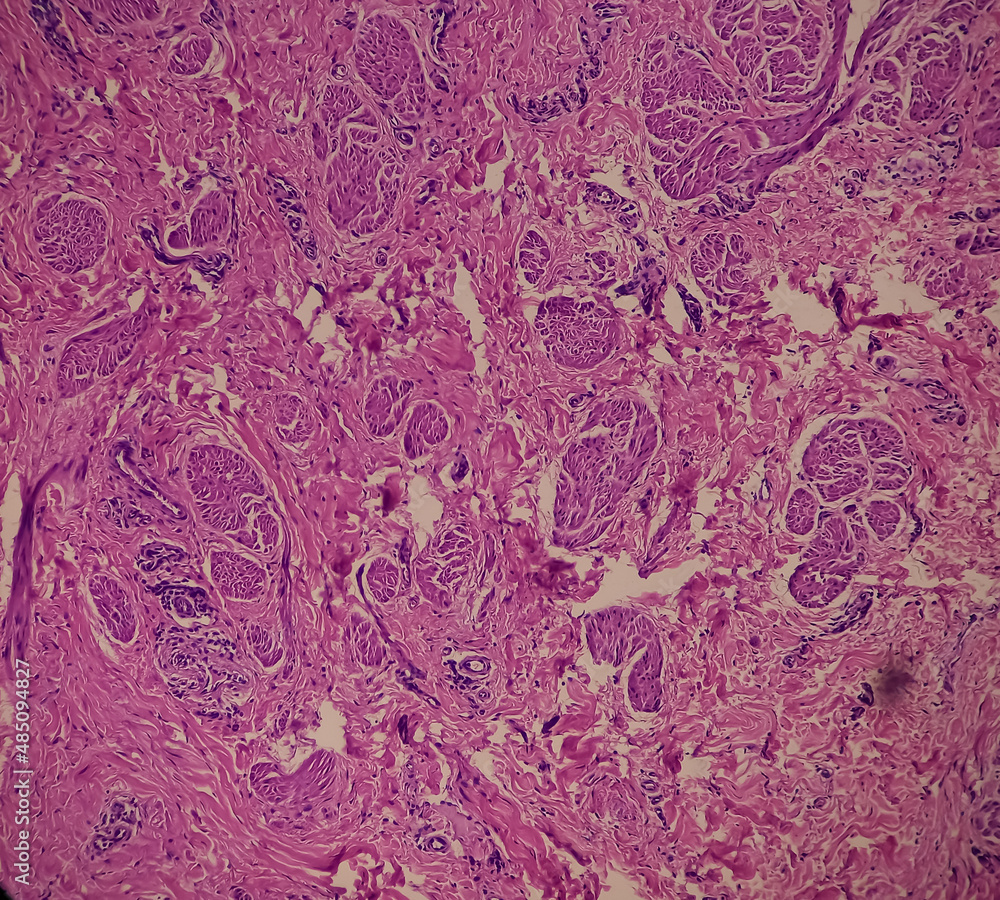

From stock.adobe.com

Nipple ulcer biopsy Paget's disease of the nipple, microscopic image Paget's Disease Nipple Stories when the small spot first appeared on her nipple, karrie morgan didn’t think much of it. It’s become a passion of mine to spread the word and make it more known about paget’s disease of the breast. paget’s disease of the breast is an uncommon type of breast cancer that usually first shows as changes to the nipple.. Paget's Disease Nipple Stories.